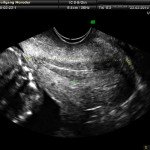

L’ecografia è una tecnica che consente di vedere gli organi del nostro corpo con l’utilizzo di onde sonore ad alta frequenza (ultrasuoni, non udibili dall’orecchio umano) che attraversano i tessuti. La sonda ecografica invia impulsi di onde sonore nel corpo. Quando le onde sonore arrivano al feto mandano degli echi: tali echi (o onde di ritorno) sono trasformati in immagini sul monitor dell’ecografo. Con l’ecografia è quindi possibile osservare in modo dettagliato il feto.

Le ragioni più comuni per cui si esegue una ecografia in gravidanza sono: determinare il numero degli embrioni o dei feti, visualizzare l’attività cardiaca fetale, determinare l’epoca di gravidanza, valutare l’anatomia e la crescita fetale, determinare la posizione del feto e della placenta

Nei primi mesi di gravidanza, con la misura della lunghezza del feto, è possibile valutare se lo sviluppo corrisponde all’epoca di gravidanza valutata in base alla data dell’ultima mestruazione, il numero dei feti e la presenza dell’attività cardiaca.

Dal secondo trimestre si misurano altre parti fetali, ed i valori di tali misure vengono confrontati con quelli delle curve di riferimento. Si può così valutare la normalità o meno della crescita fetale. Inoltre periodo si visualizzano la sede di inserzione placentare e la quantità di liquido amniotico.

A fianco alla più tradizionale ecografia eseguita per via transaddominale, risulta particolarmente utile nell’esame ecografico ostetrico e ginecologico la via di accesso transvaginale.

Con questa metodica, utilizzando delle sonde ecografiche appositamente predisposte (per forma e dimensione, e per frequenza di emissione degli ultrasuoni) è possibile controllare la gravidanza nel primo trimestre con una qualità e definizione d’ immagine nettamente superiori a quanto possibile per via transaddominale.

Con il finire del primo trimestre per il controllo ecografico di routine della gravidanza la via transvaginale viene poi sostituita dalla via transaddominale.

Successivamente può risultare utile il ricorso all’ ecografia transvaginale nei casi in cui si sospettino delle modificazioni precoci (raccorciamento) del collo dell’utero, come potrebbe verificarsi nei casi di minaccia d’ aborto o di parto pretermine.

In questi casi infatti è possibile con l’ ecografia misurare con precisione la lunghezza del collo uterino. In questi casi inoltre l’ ecografia può anche evidenziare un’ iniziale dilatazione dell’ orifizio uterino interno. Tali modificazioni del collo dell’ utero, valutabili con accuratezza solo con l’ ecografia transvaginale, hanno una grande importanza nel considerare un eventuale rischio di parto pre-termine.